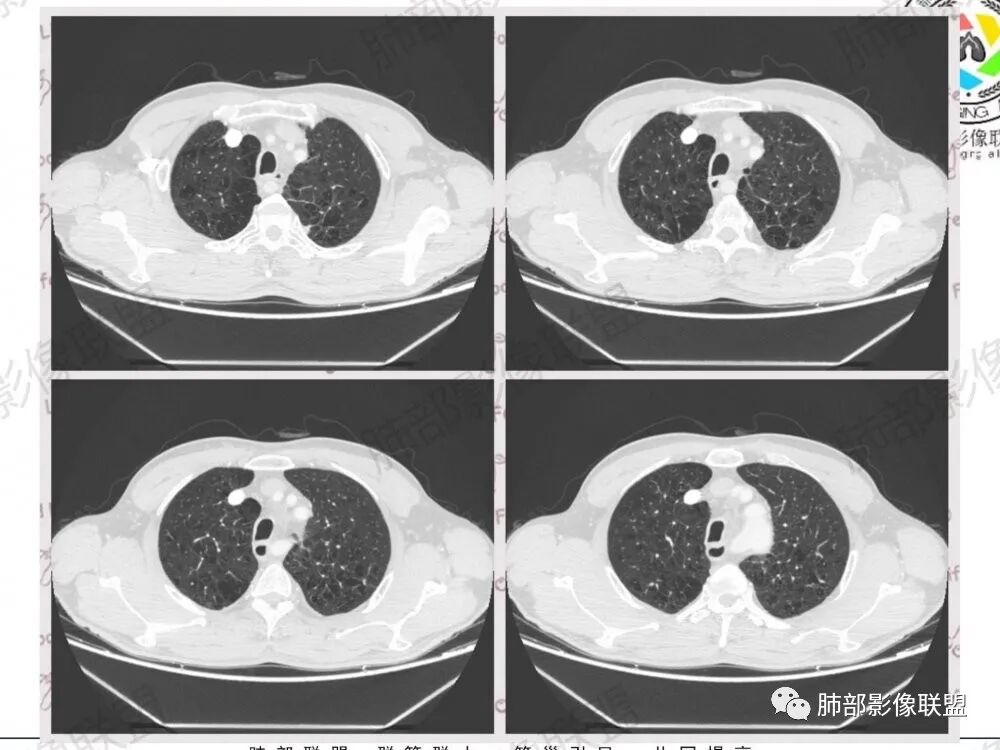

1.左肺门及纵隔见异常增大淋巴结,部分融合,不均匀轻度强化,未见明显坏死。

肿大淋巴结与纵隔血管等结构“无缝”贴合。

2.纵隔增宽但依旧居中。

1.这应当是常见的小细胞肺癌的转移方式。

别忘了,患者左肺上叶那个略显饱满的的小结节,有理由相信那是发源地。

因为这些符合肺癌的整个转移路径!